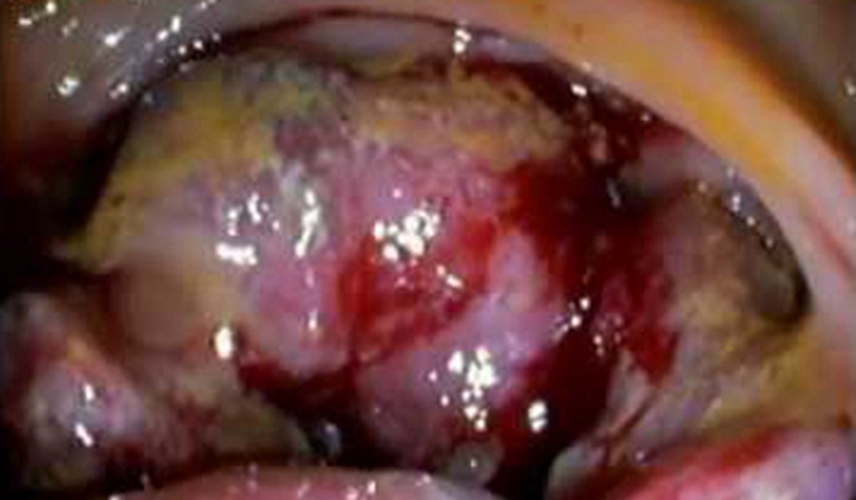

乙狀結腸癌潰瘍型症狀